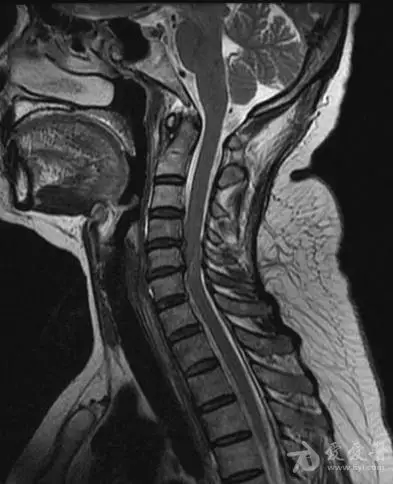

原创:颈椎病各种表现情况 图文介绍